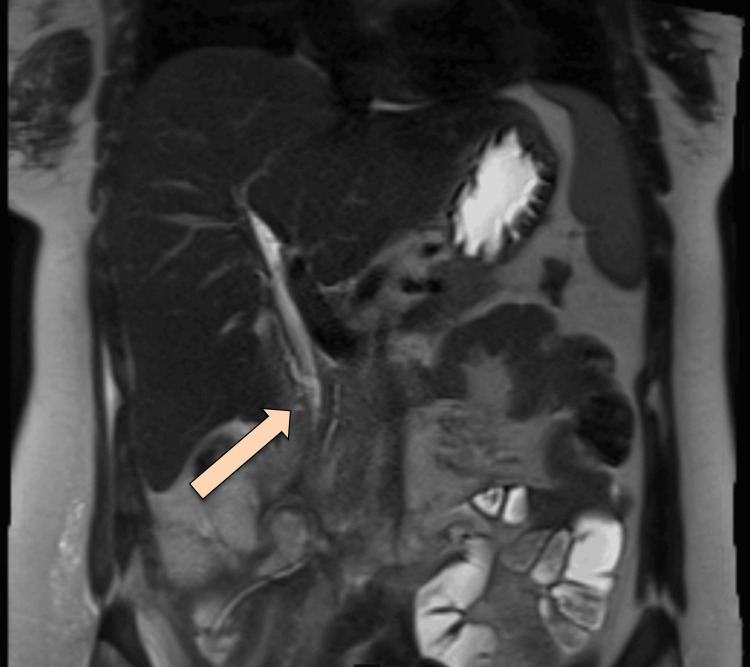

After the lungs were fully expanded in the chest X-ray, the chest tube was removed. The plan was to proceed with an MRCP Promovist to assess for a persistent biliary leak. Pooling/extravasation of Primovist into the retroperitoneal collection was observed, with the injury site likely at distal CBD at the level of the ampulla of Vater. The stable size of the multiloculated air-containing retroperitoneal collection was noted, with features suggesting a superadded infectious process (Figure 5).

MRCP was repeated, which showed delayed phases of the hepatocellular agent demonstrating opacification of the biliary tree with contrast reaching the second part of the duodenum without evidence of contrast leakage. However, 12 hours of delayed images showed a faint high signal at the expected site of the collection, possibly representing a persistent biliary leak. No significant biliary duct dilatation was observed. Expected minimal pneumobilia was noted (Figure 8).